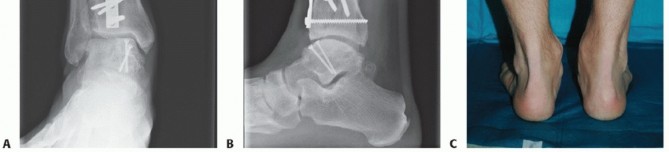

Patient is a 40-year-old man with chronic ankle pain failing prior arthroscopic débridement and microfracture. Feels he is overloading lateral border of foot.

Preoperative weight-bearing radiographs suggest large medial OLT and varus malalignment with some varus talar tilt (TECH FIG 5A,B).

CT demonstrates large-volume medial OLT (TECH FIG 5C-E).

- TECH FIG 5 • A,B. Preoperative radiographs. A. AP and mortise ankle views suggest large medial talar dome OLT and varus alignment. B. Lateral radiograph. C-E. Preoperative CT of largevolume OLT. C. Coronal view. D. Sagittal view. E. Axial view.

We routinely obtain simulated weight-bearing radiographs at 6 and 10 weeks and again at 14 to 16 weeks, depending on the progression of healing. If there was a concern about fixation of the graft or osteotomy, then radiographs are also obtained at the first postoperative visit (FIGS 1 , 2 and 3).

FIG 1 • Two-and-a-half-year follow-up. A. AP radiograph. B. Lateral radiograph. C. Clinical correlation.*

FIG 2 • Dorsiflexion. A. Radiograph (although the joint appears to narrow anteriorly, this phenomenon has not changed in 2 years and the patient experiences no pain or impingement). B. Clinical appearance.*

FIG 3 • Plantarflexion. A. Radiograph. B. Clinical correlation.*